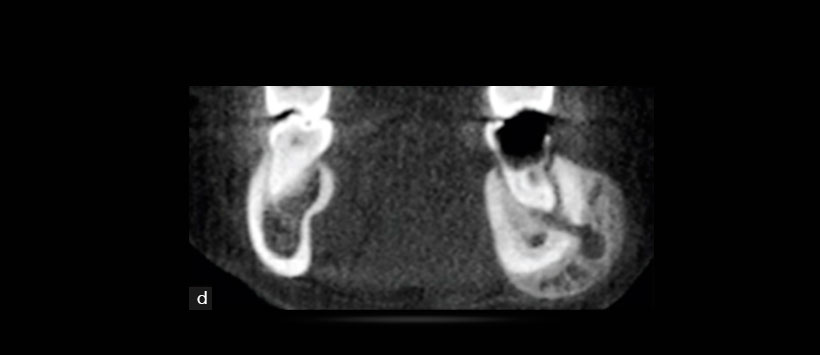

Figura 3: Vista coronal de la tomografía computarizada de haz cónico que muestra lesión de caries con compromiso pulpar en pieza 3.6 con proceso osteolítico periapical y trayecto fistuloso hacia la zona vestibular asociado a una severa reacción periostal a nivel de la tabla vestibular con extensión al reborde basal mandibular. Se aprecia ademas un aumento de la densidad ósea circundante.